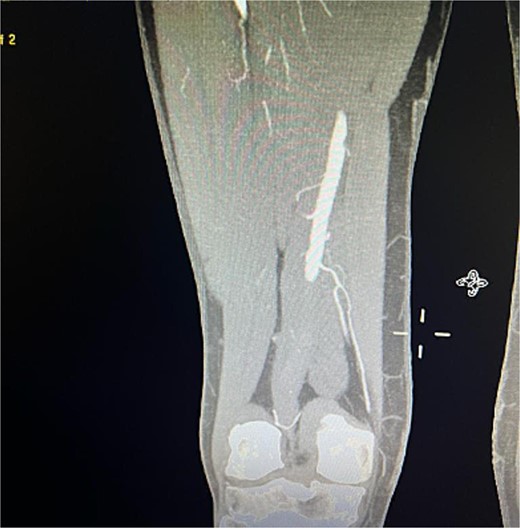

The patient presented 2 months after the initial procedure to the emergency department with burning pain and pallor in his right leg. On physical examination, there was pallor below the knee in addition to loss of pulsation. Physical examination revealed loss of pulsation below the knee. CT angiography (CTA) showed total occlusion of the popliteal artery without any endoleaks, prompting an urgent transpopliteal embolectomy. Trans-esophageal Echocardiography and CTA of the aorta were performed to rule out other sources of embolization, revealing a thrombus adherent to the wall distal to the stent graft (Fig. 3). The patient was started on warfarin.

CTA scan showing the floating thrombus distal to the right iliac artery stent, following the patient presenting with acute embolic ischemia in the right leg.